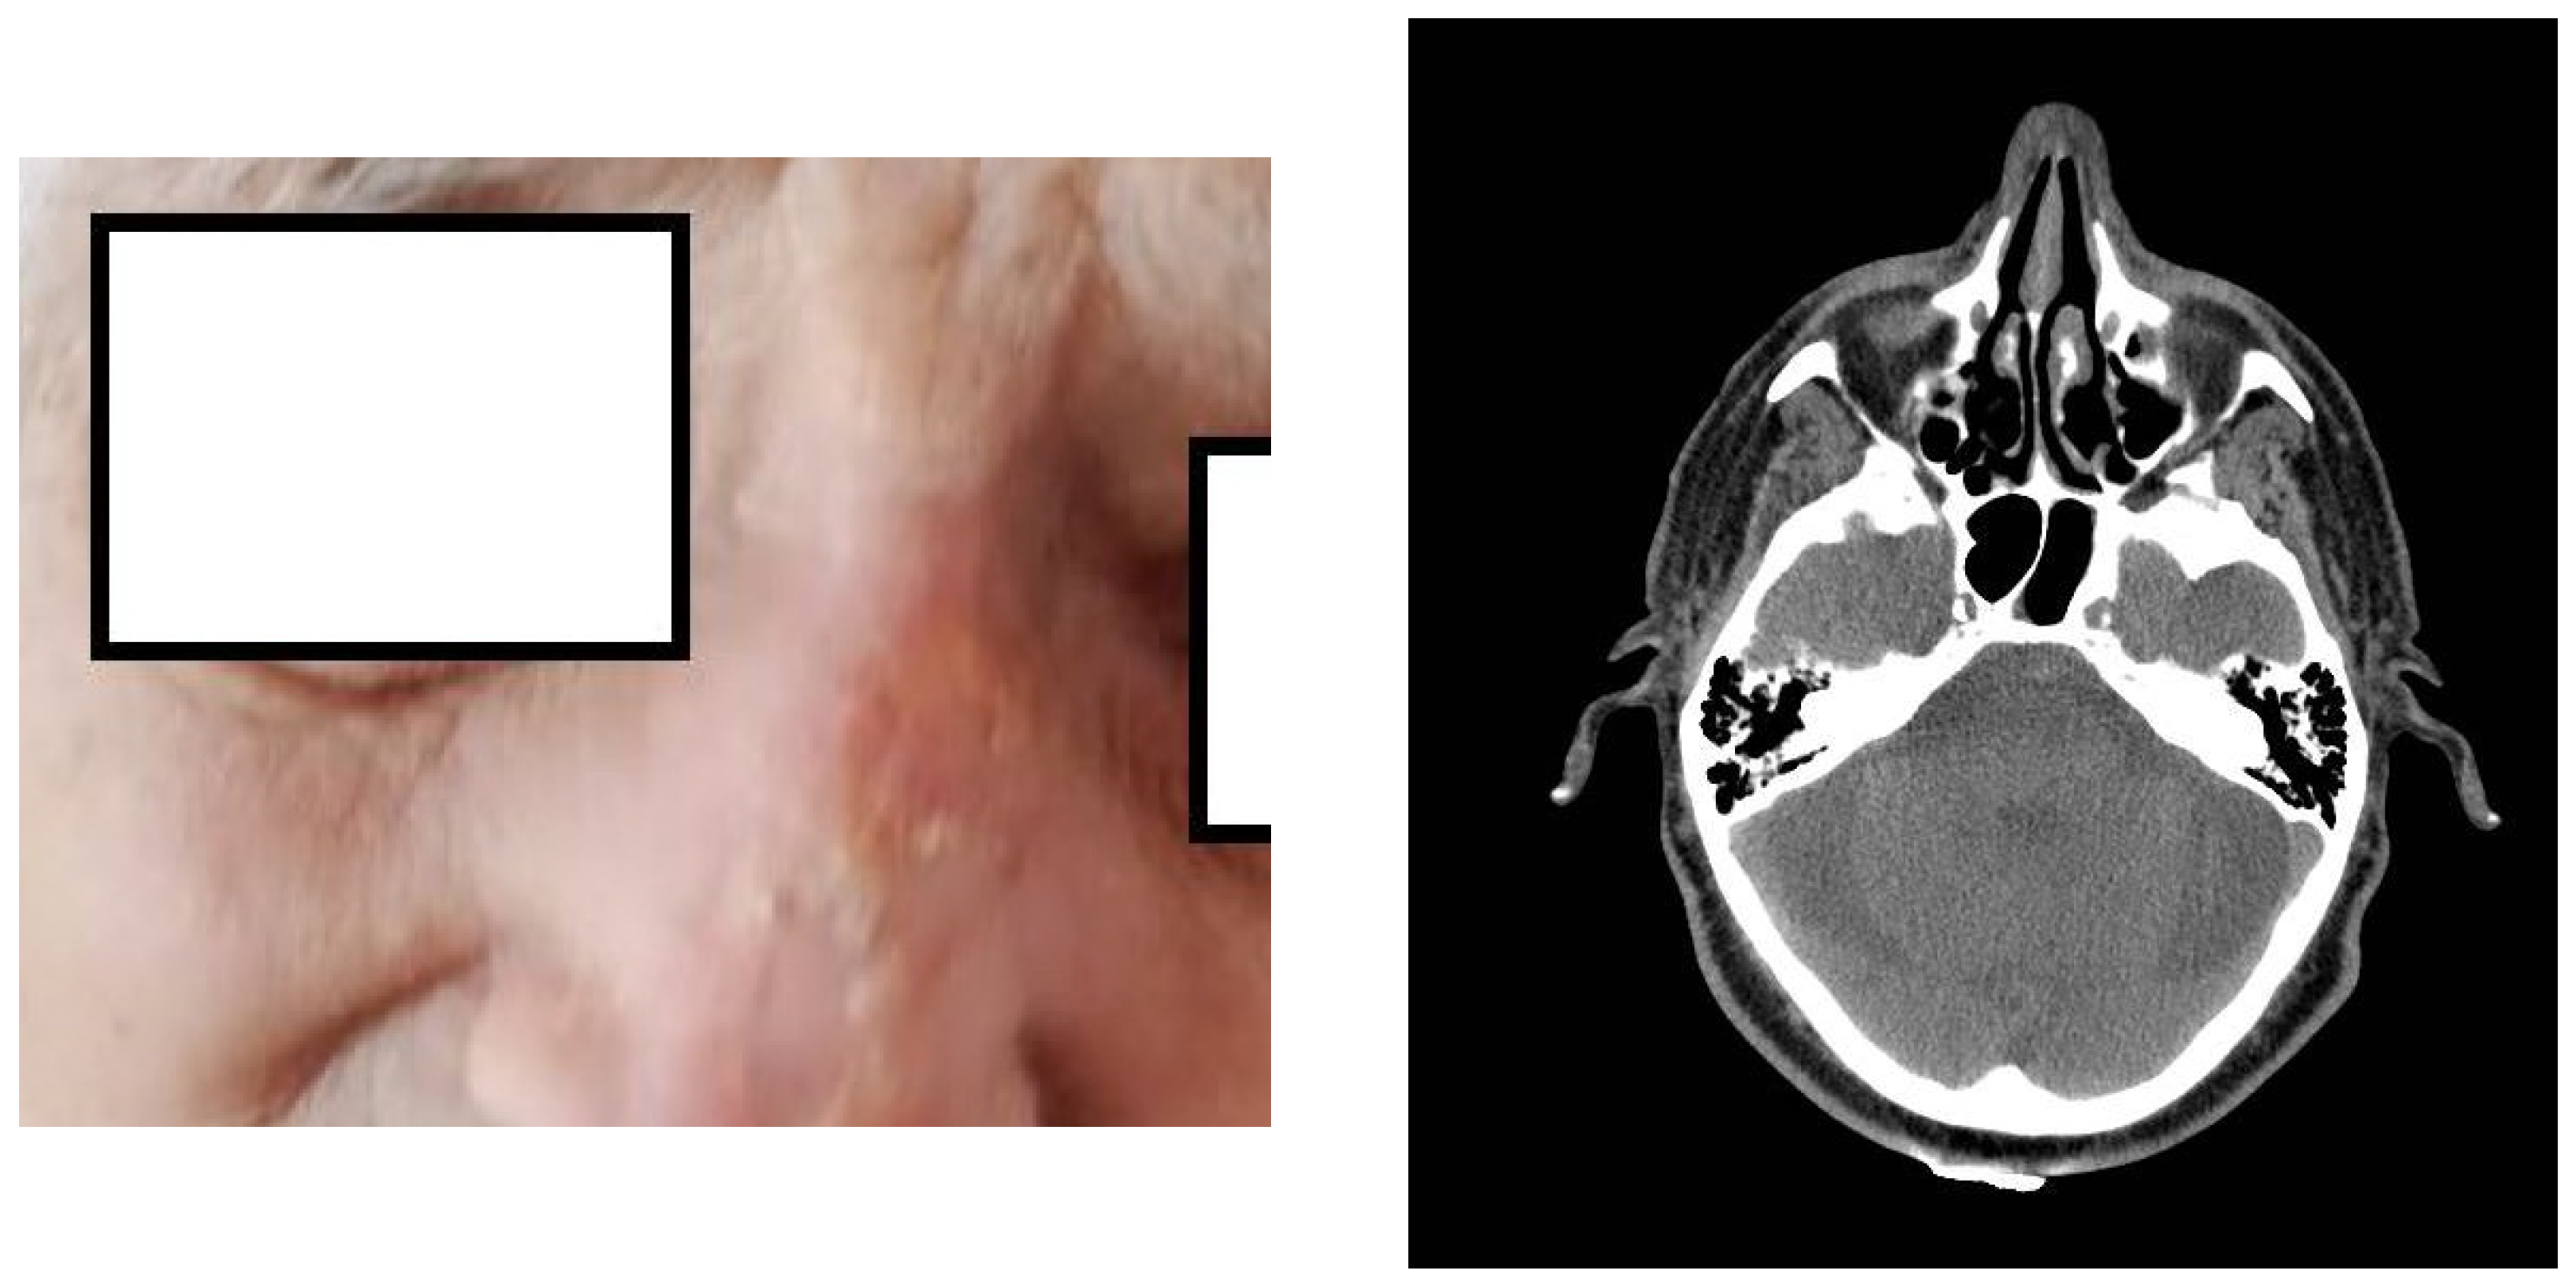

2. Presentation of the Case